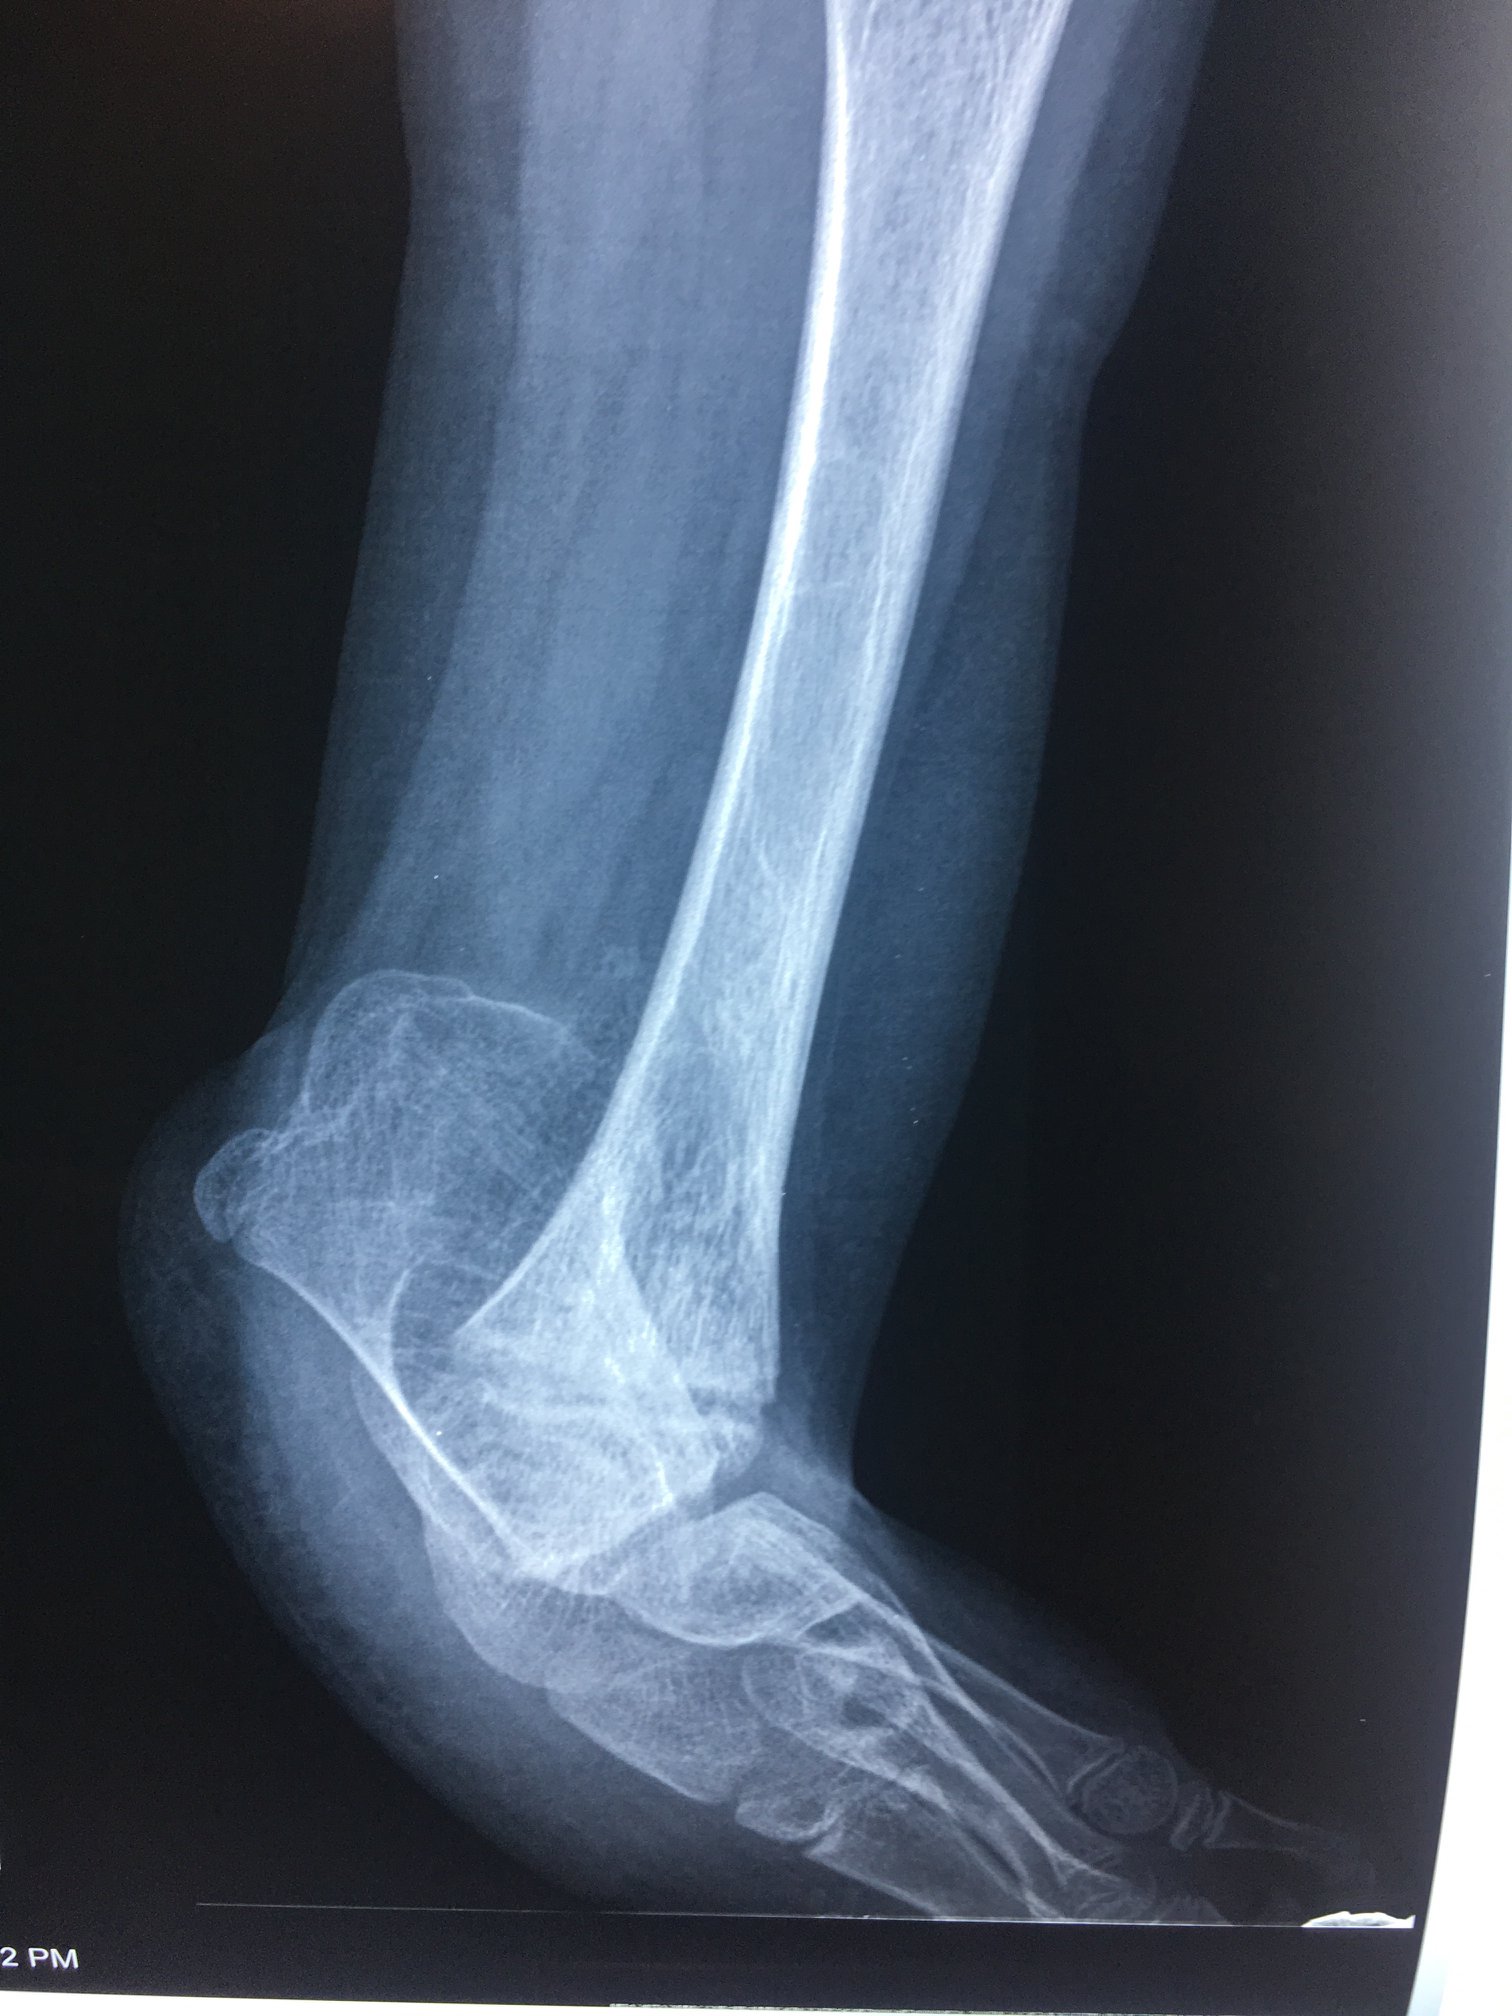

Ausencia congenita del peroné

A los papás de Lazarito les dijeron en Estados Unidos que la única alternativa para su hijo era una amputación; buscando segundas opiniones, llegaron conmigo. Lazarito, de 13 años, tiene #hemimelia #perónea, una ausencia congénita del peroné que causa malformaciones y acortamientos. Para evitar la amputación, se le realizó una reconstrucción del tobillo y alineamos su pierna de forma funcional. Ahora, mi pacientito ya camina con apoyo al 100%, realiza sus actividades diarias y dice que empezará a jugar fútbol. Agradezco a sus papás por la confianza y a sus familiares en Guadalajara por recomendarlo conmigo.